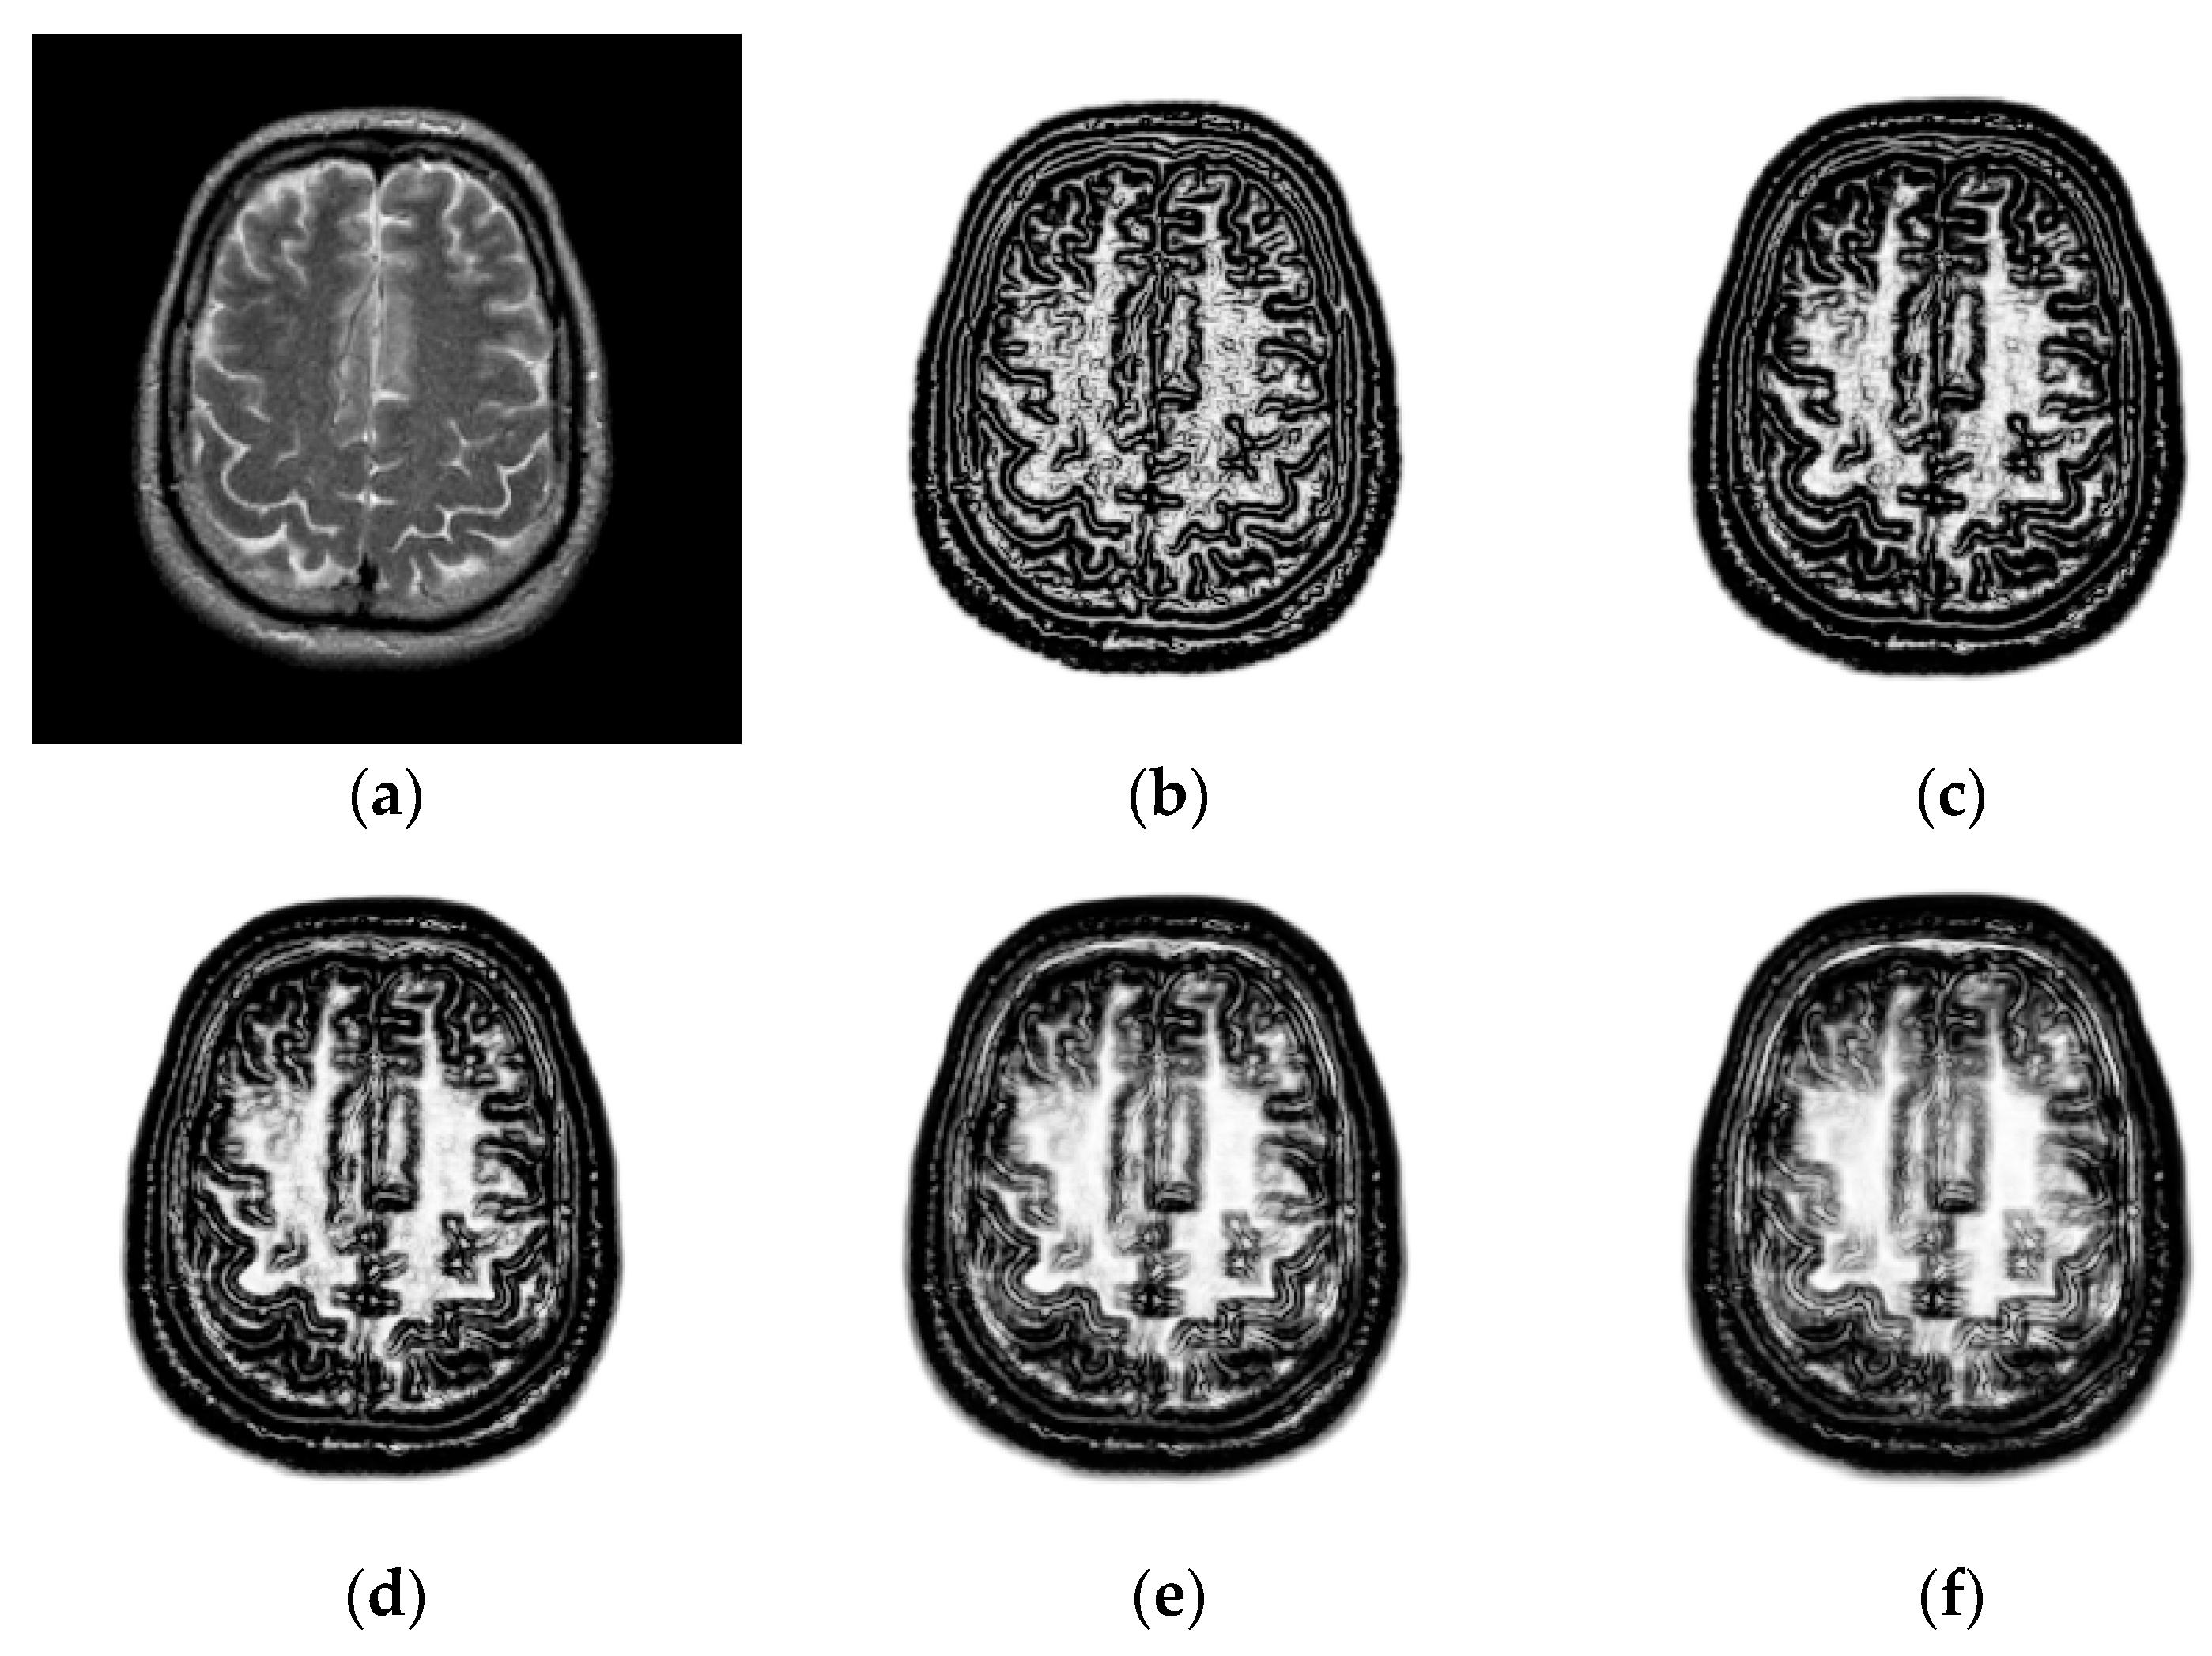

2.2. Structural Representation

3.1.1. Impact of the Patch Size